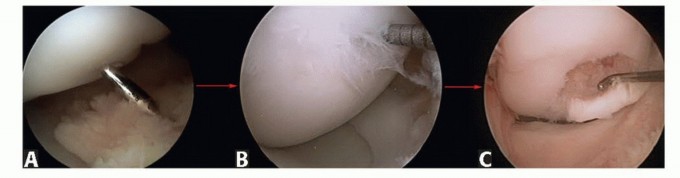

DEFINITION The term osteochondral lesion of the talus (OLT) refers to any pathology of the talar articular ca…

DEFINITION Osteochondral lesion of the talus (OLT) may cause significant pain and mechanical symptoms in the …